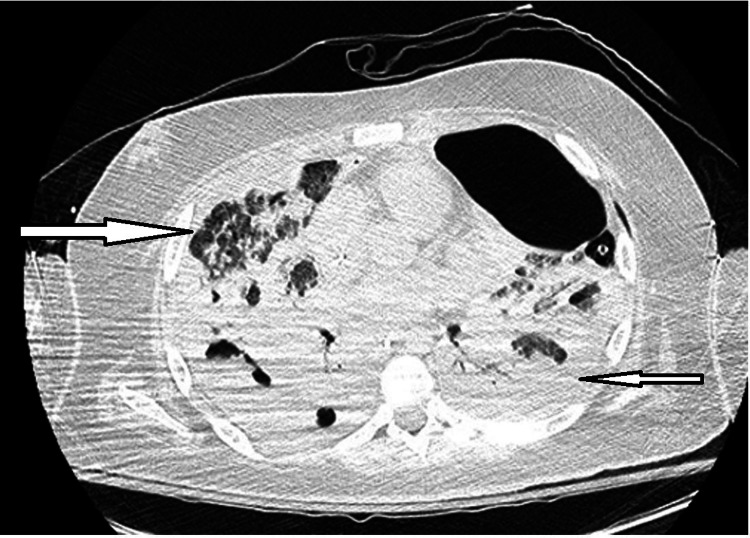

Computed tomography of the chest showed bilateral pleural effusions, areas of diffuse ground-glass opacities in the upper lung fields, cystic necrosis and bibasilar cavitations (Figure 1).